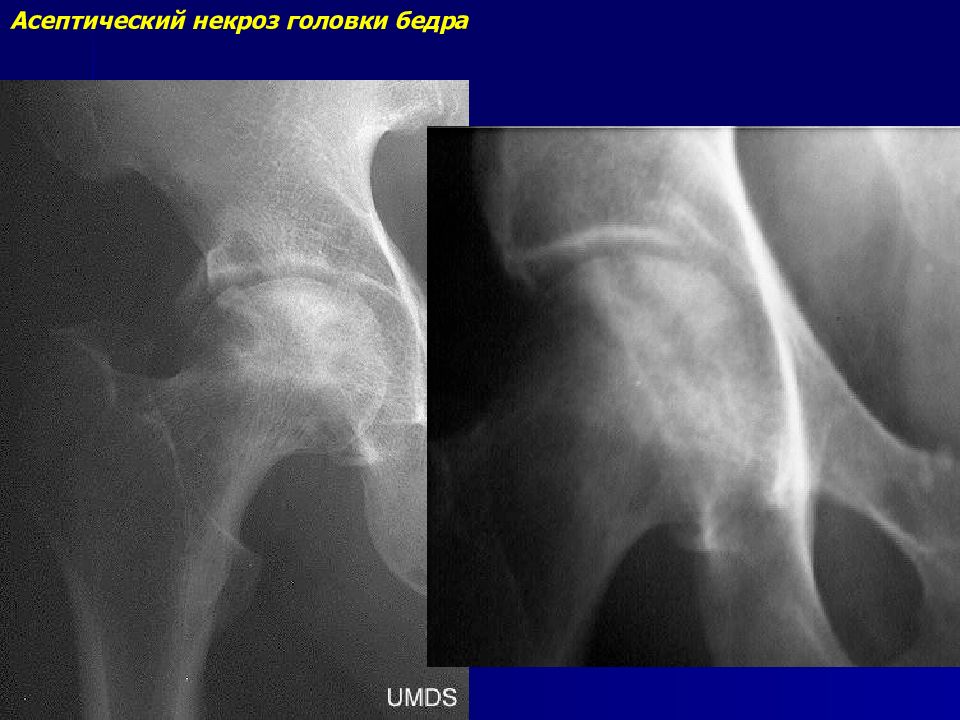

Диагностика ТБС рентгеном и асептический некроз: особенности лечения

Раздел: Снимки-откровения